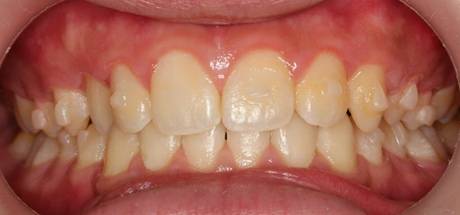

インビザGOによる矯正症例1 16歳男性

4か月後。犬歯が外側に出てきました